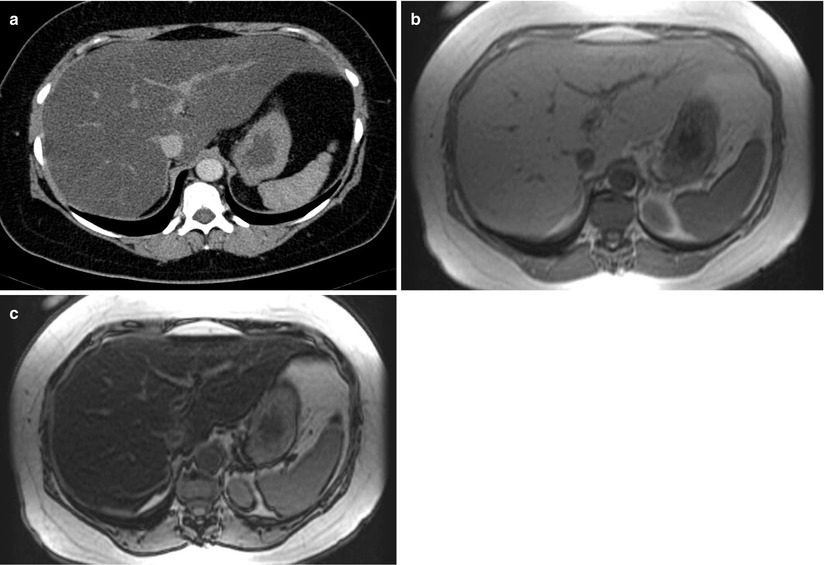

59-year-old diabetic male with elevated alkaline phosphatase ...

Imaging of Diffuse and Inflammatory Liver Disease | SpringerLink